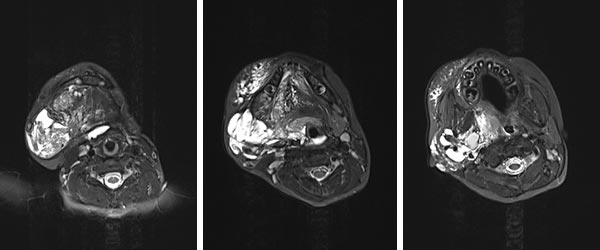

In der MRT (axial; T2-Wichtung; fettunterdrückt) im 2. Lebensjahr zeigt sich die lymphatische Malformation als stark hyperintense (weiße) Raumforderung. Die Ausdehnung reicht bis in die tiefen Halsweichteile, Oropharynx und Hypopharynx sind deutlich eingeengt. Hier droht eine Verlegung der oberen Atemwege bei Zunahme der Schwellung. Dies kann fatal sein.

Die axiale T2-gewichtete, fettgesättigte MRT im 6. Lebensjahr, nach insgesamt 4 Sklerosierungen, zeigt eine klare Besserung insbesondere der makrozystischen Anteile der lymphatischen Malformation. Augenfällig ist auch der positive Effekt auf die oberen Luftwege, die jetzt nicht mehr eingeengt sind.